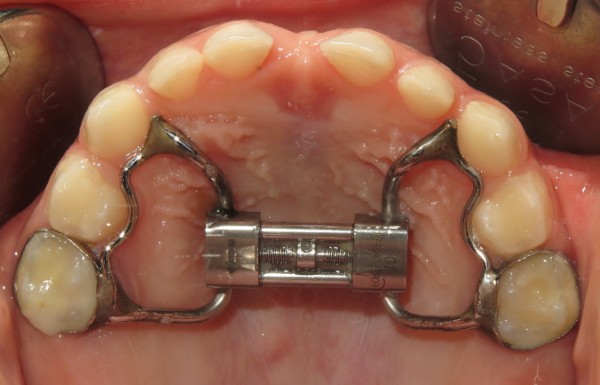

Nong hàm cố định

Đây là kỹ thuật sử dụng khí cụ cố định gắn trực tiếp vào răng để duy trì hoặc mở rộng khung hàm lâu dài. Phương pháp này phù hợp với những bệnh nhân cần mở rộng nhanh, cần độ chính xác cao.

Khí cụ cố định giúp hạn chế việc tháo lắp không đúng quy trình, từ đó nâng cao hiệu quả điều trị. Trong quá trình thực hiện, bác sĩ sẽ kiểm tra định kỳ để điều chỉnh khí cụ phù hợp với mức độ mở rộng mong muốn.

Phương pháp này thích hợp cho cả trẻ em và người trưởng thành, đặc biệt khi những phương pháp khác không đạt đủ hiệu quả hoặc bệnh nhân cần kết quả rõ rệt hơn trong thời gian ngắn.

Nong hàm chậm / RPE (Rapid Palatal Expander)

Đây là một trong những kỹ thuật phổ biến nhất hiện nay, dựa trên nguyên lý mở rộng nhanh vòm miệng bằng khí cụ RPE. Phương pháp này được thiết kế để tạo ra lực mở rộng đều đặn trong thời gian ngắn, giúp nhanh chóng điều chỉnh cấu trúc hàm mặt.

Chỉ định của RPE rất rộng rãi, đặc biệt phù hợp với trẻ em, thanh thiếu niên còn đang trong giai đoạn phát triển xương. Quá trình này thường kéo dài từ 3-6 tuần, tùy vào mức độ cần mở rộng.

RPE giúp cải thiện đáng kể các vấn đề về khung xương, đồng thời thúc đẩy phát triển mặt cân đối toàn diện. Chính vì thế, phương pháp này ngày càng trở nên phổ biến hơn trong cộng đồng nha khoa hiện đại.